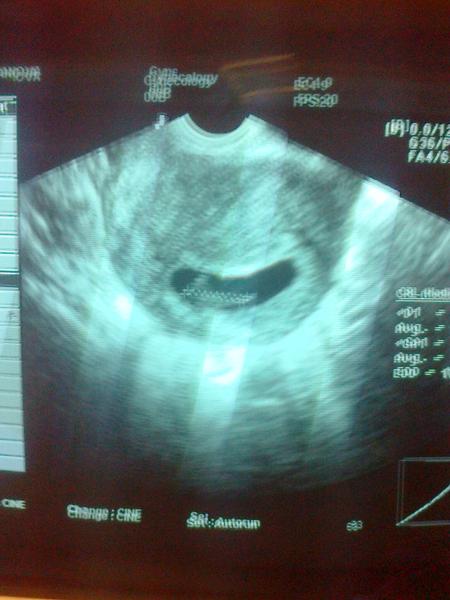

@stastenka42 s takou malou dusickou som liezla na kozenku.Verime ze tentokrat to dotiahneme do uspesneho konca.Doktorka sa ma pytala ze kolky pokus ja ze 5 a ona ze pozna aj ze to vyslo na 9 pokus a ja ze a ja poznam jednu babulku ktorej to vyslo na 13 pokus a ona ze stoji to za to a hodila jeden krasny usmev 🙂